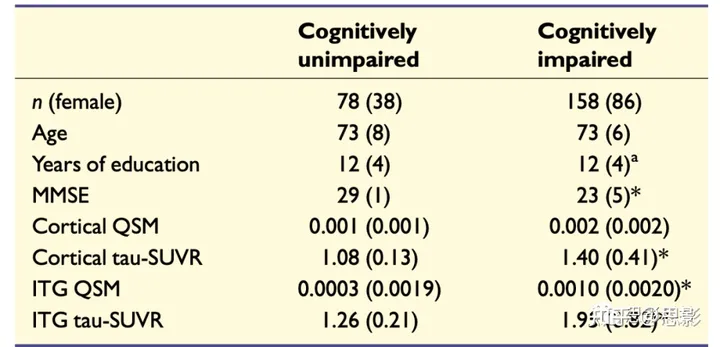

瑞典BioFINDER-2研究的236名参与者被纳入(详见补充材料中的纳入和排除标准)。只有那些通过脑脊液生物标志物证据显示有脑淀粉样病变(异常的淀粉样β42/40比率)的参与者才被纳入研究队列,这些参与者包括78名认知未受损的淀粉样β阳性受试者和158名认知受损患者。后一组由77名被诊断为轻度认知障碍的淀粉样β阳性患者和81名阿尔茨海默病痴呆患者组成。参与者的人口统计和临床特征总结在表1中。所有受试者都根据《赫尔辛基宣言》提供了书面知情同意,该研究已得到瑞典隆德的伦理审查委员会的批准。

表1:研究队列的人口统计学总结

值以平均值(标准差)给出。使用 χ2 和 Mann-Whitney U 测试比较了人口统计因素和临床特征(性别:χ2 = 0.47,P > 0.4;年龄:U = 5934,P > 0.3;教育年数:U = 6062,P > 0.4;MMSE:U = 881,P < 0.001;皮质QSM:U = 5515,P = 0.095;皮质tau-SUVR:U = 2396,P < 0.001;ITG QSM:U = 4628,P < 0.01;ITG tau-SUVR:U = 2181,P < 0.001)。

*与认知未受损组明显不同。MMSE = 迷你精神状态检查。a三个数据点缺失。